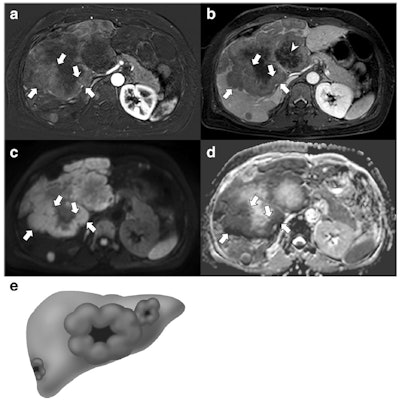

A 49-year-old woman with a gallbladder neuroendocrine tumor. A and B: On subtraction imaging of arterial phase and delayed phase of axial contrast-enhanced MRI, a 14.7-cm mass replacing the gallbladder and invading the liver is demonstrated. The mass shows thick rim enhancement with a thick peripheral enhancement and washout (arrows). Note the delayed central enhancement (arrowhead). On diffusion-weighted imaging (C) and apparent diffusion coefficient mapping (D), this mass also depicts a thick rim diffusion restriction (arrows). The diagnosis of neuroendocrine tumor was made via percutaneous biopsy. E: Thick rim appearance. All images courtesy of Drs. Jae Seok Bae, Se Hyung Kim, and colleagues and European Radiology."Neuroendocrine tumors and their metastases to the liver and lymph nodes more frequently demonstrated a thick rim appearance on contrast-enhanced MRI and diffusion-weighted images," they reported. "The ratio of apparent diffusion coefficient values between the lesion and the spleen was significantly lower for the primary mass, liver metastases, and lymph node metastases of GB-NETs than for those of GB-ADCs. A large metastatic lymph node was the only poor prognostic factor for overall survival in patients with GB-NETs and GB-ADCs."